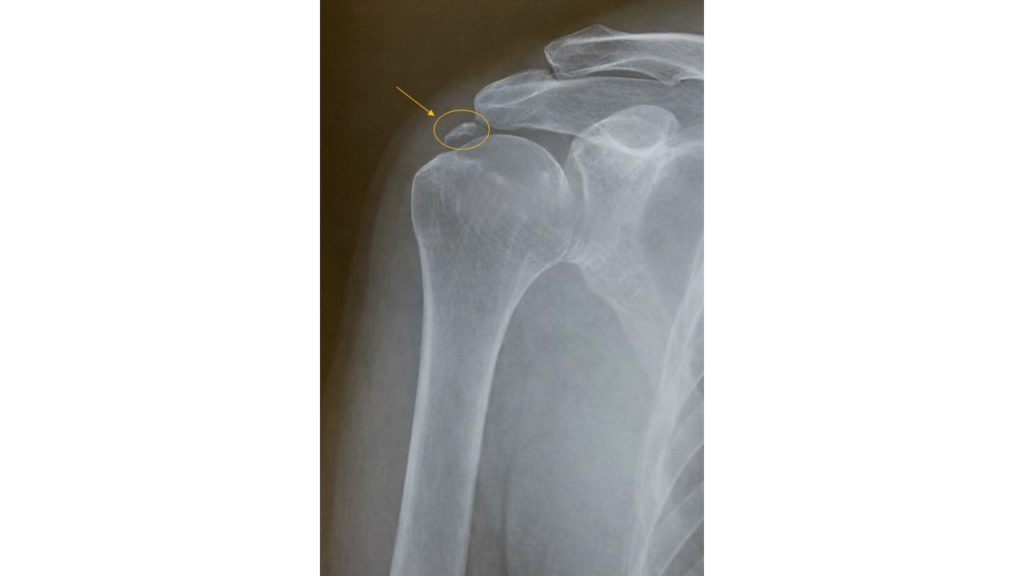

石灰沈着性肩関節炎は、肩の腱板にリン酸カルシウム結晶(石灰)が沈着し、炎症を起こす病気です。

40〜50代の女性に多く、安静時の痛みや夜間の痛みを訴えられる方が多いです。

これは肩関節に石灰が沈着することによって炎症による痛みが出るのですが、臨床的には石灰が溜まっている

場所だけに痛みが出る訳ではなく上腕下部や、背中の方にも放散痛を訴えられている印象もあります。

特にこれといった原因がなく、急激な肩周辺の痛みが出て来た場合には一度検査をお勧めします。

検査は石灰沈着であればレントゲンで診断が可能です。

レントゲン撮影で石灰の影が映らなかった場合は腱板損傷や関節唇損傷などの可能性もありますので